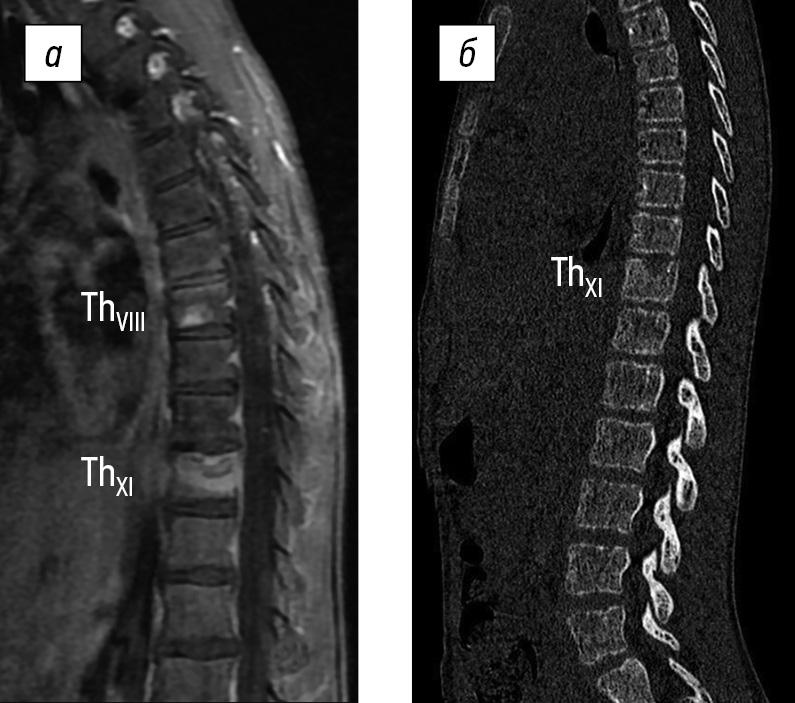

During the first visit to the Research Center, which occurred 2 months after the disease onset, an MRI review was conducted using T1-weighted imaging, T2-weighted imaging, and short-tau inversion recovery mode, supplemented with computed tomography (CT). The review revealed a lytic lesion of the ThXI vertebral body and a hyper-MR signal of the ThVIII vertebral body. The diagnosis was undifferentiated spondylitis. The patient was admitted to the Research Center’s department for further examination and trepanobiopsy with morphological verification of the condition (Fig. 1).

Fig. 1. Magnetic resonance (a) and computed (b) tomograms of the thoracolumbar spine with signs of spondylitis of ThVIII and ThXI vertebral bodies 2 months after disease onset (from the Turner Research Center for Pediatric Traumatology and Orthopedics’ archive)